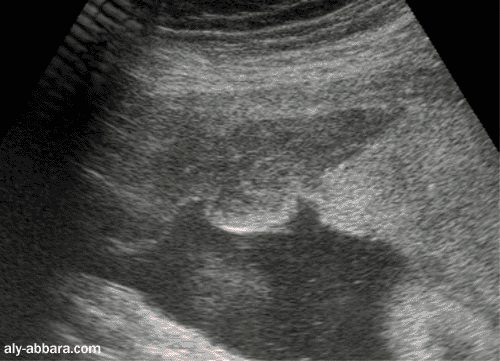

Hématome rétroplacentaire

marginal

à 34 semaines d'aménorrhée

On peut distinguer sur cette image

échographique la présence d'un décollement

prématuré

d'un placenta normalement inséré (DPPNI) avec la formation

d'un

hématome rétroplacentaire à la marge du placenta, puis une extension de

l'hématome

entraînant un

large décollement des membranes